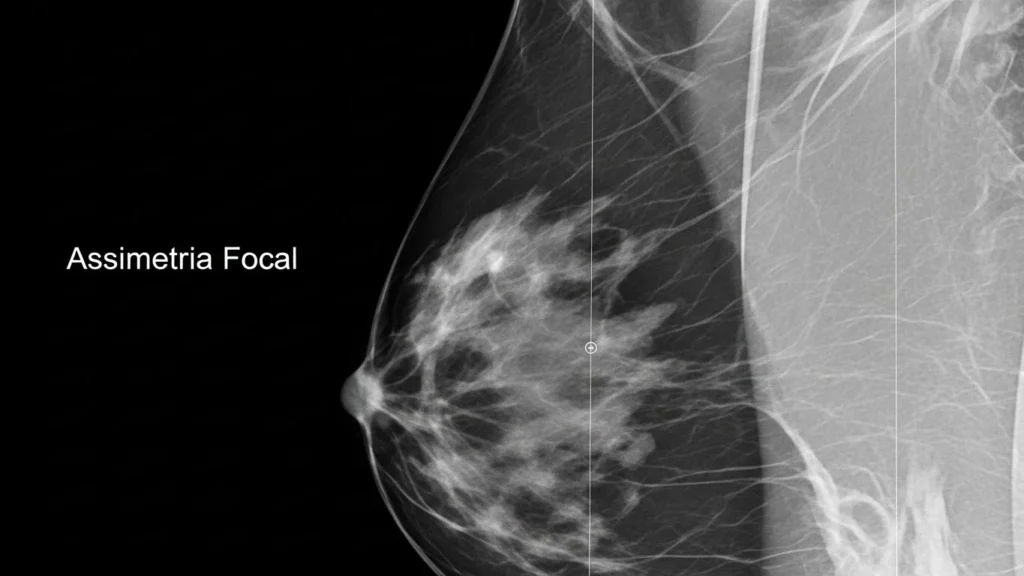

A assimetria focal é uma área do tecido mamário que aparece mais densa em relação ao restante da mama ou quando comparada à mama contralateral.

• Diferente de uma massa, não apresenta margens bem definidas.

• Pode ser vista em apenas uma incidência da mamografia ou em mais de uma — o que muda sua interpretação.